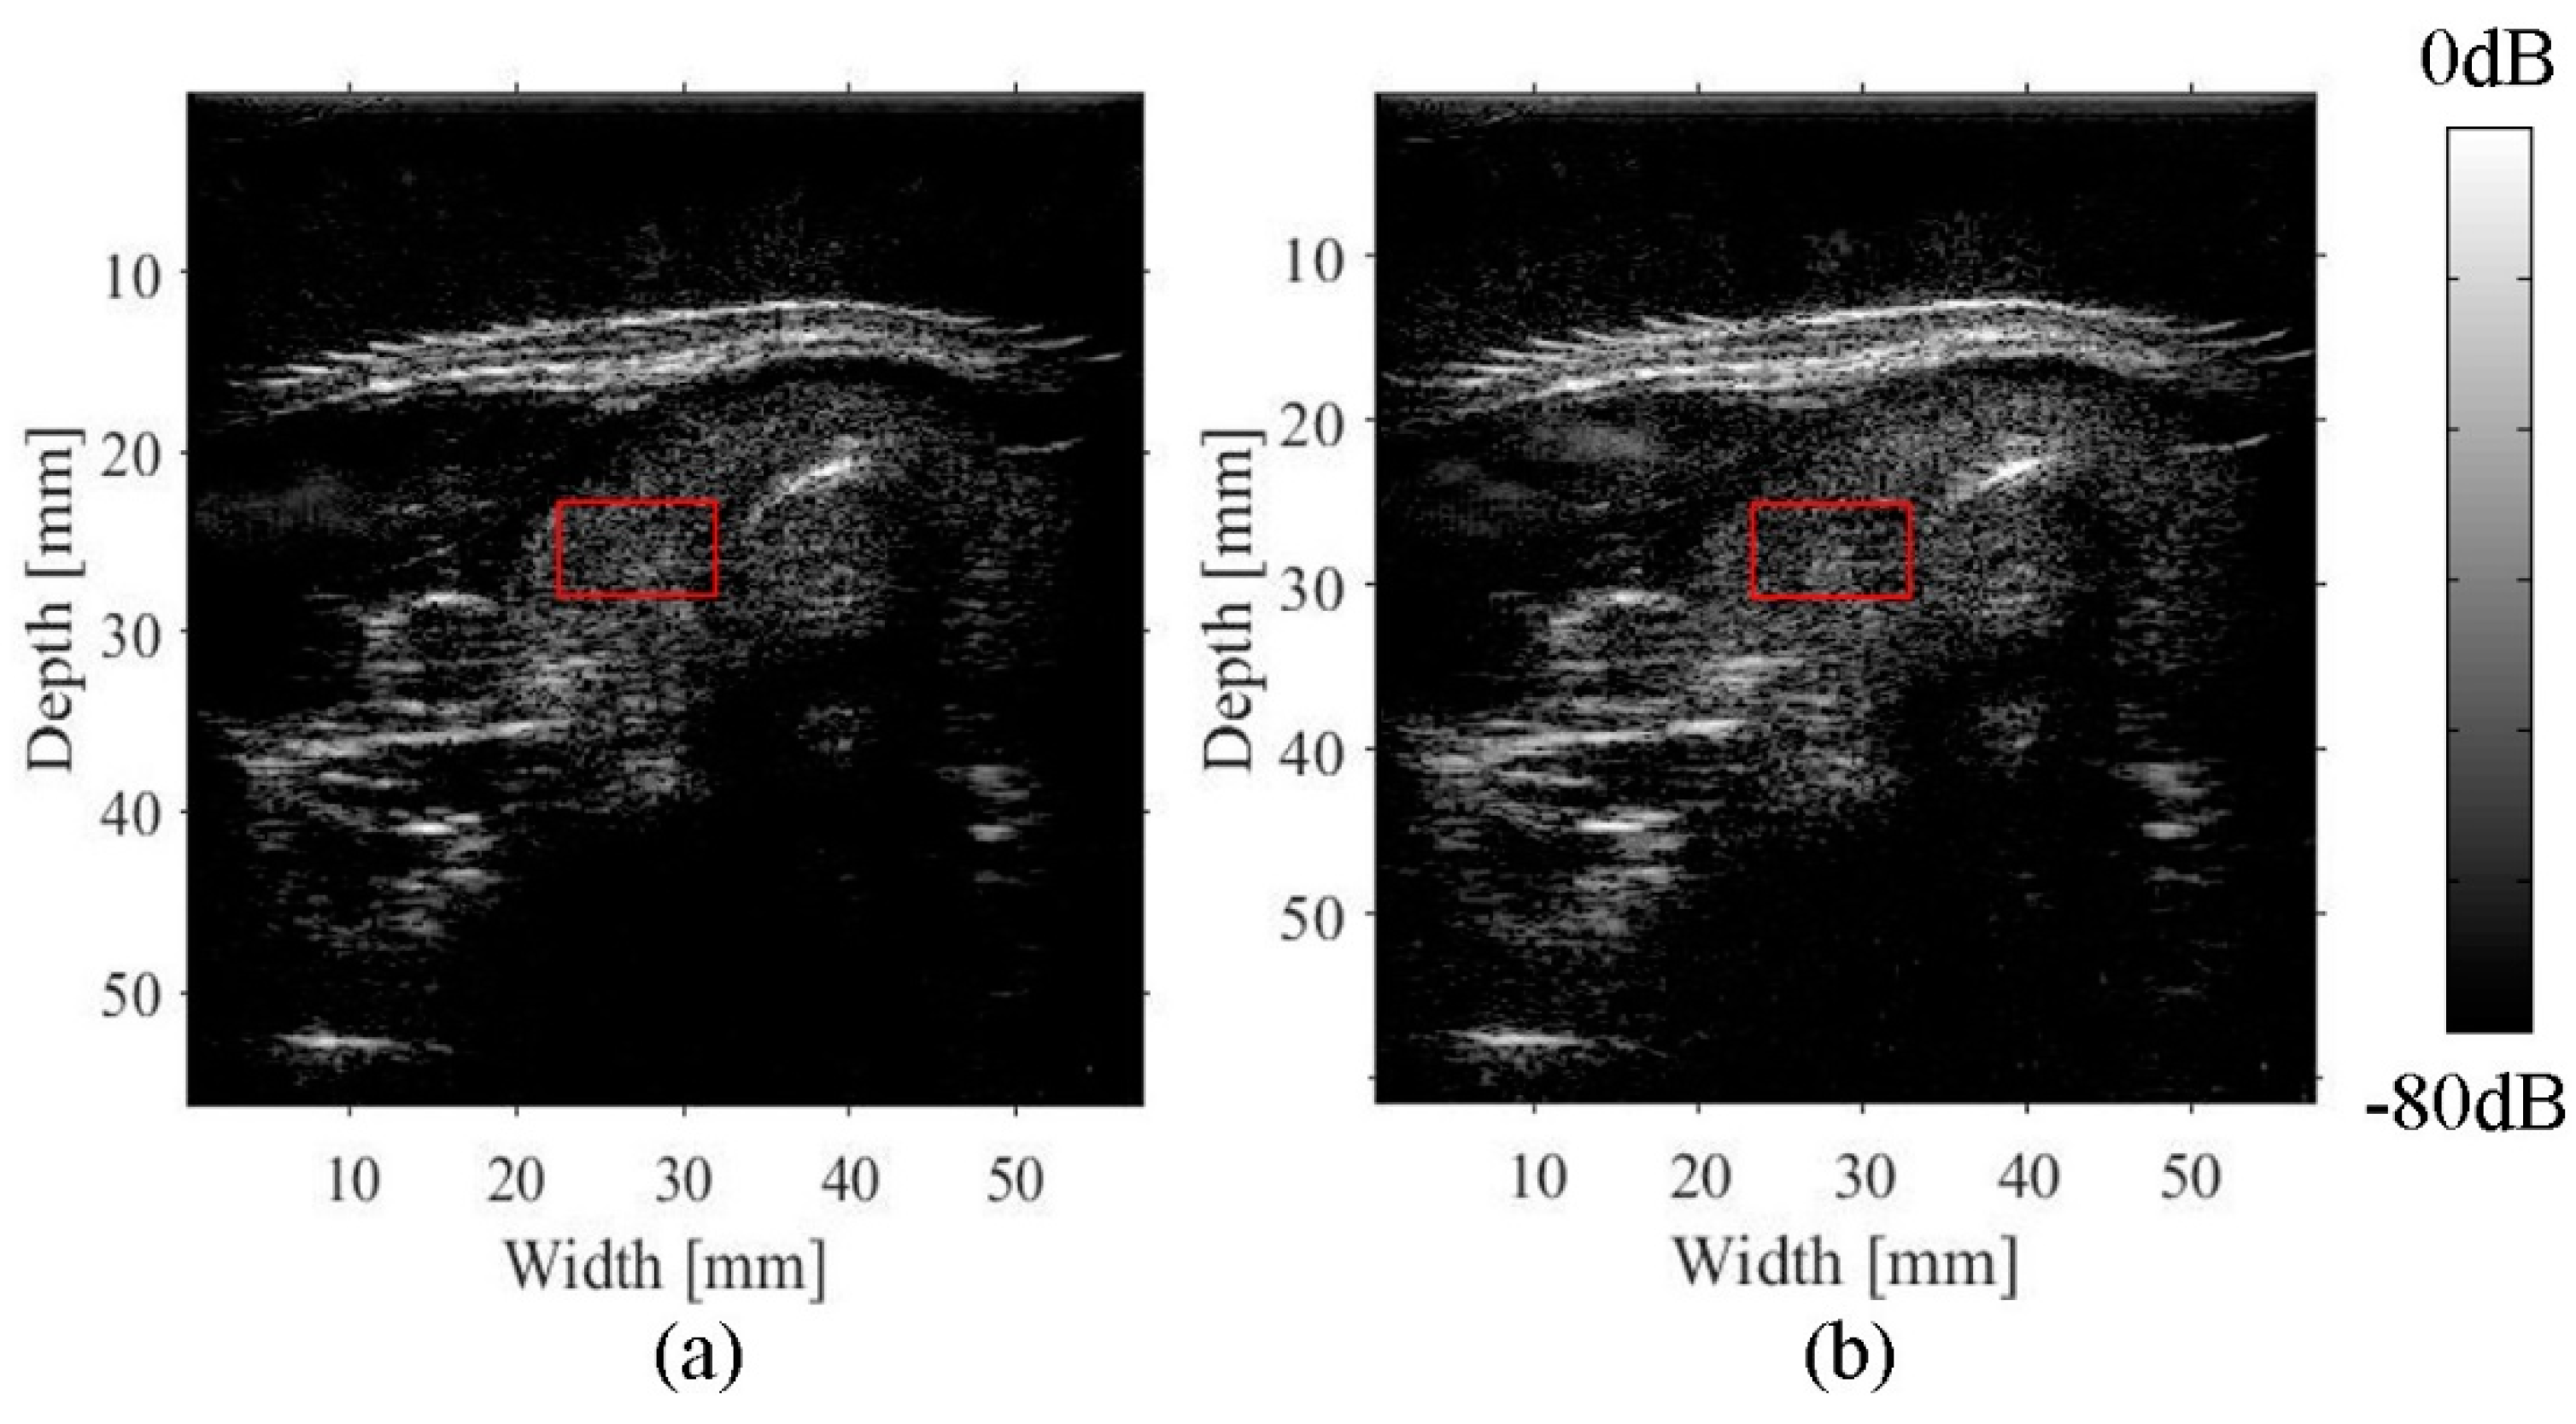

2.5. Experimental Imaging of the Human Neck

3.3. Imaging of the Neck